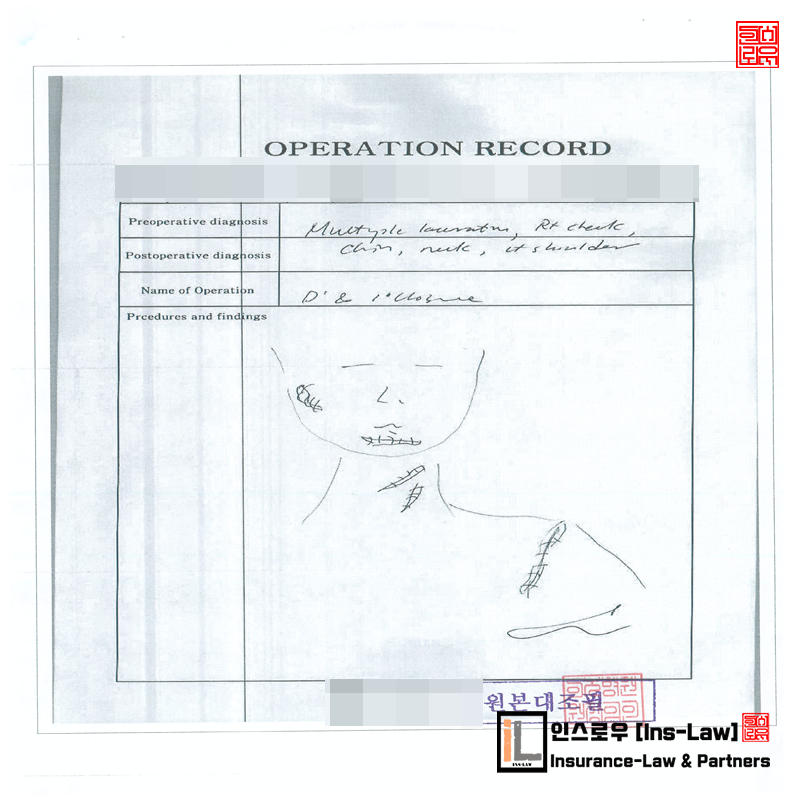

친구와 저녁 식사를 하고 도로 건너편으로 횡단하다가 차량과 충격하였고 119 긴급자동차로 인근 대학병원에서 수술 및 치료과정중에 면담을 통하여 수임할 수 있었던 사례입니다.

■ 치료내용 및 치료에 대한 병원소견

병원에서 시행한 자기공명영상 검사상 상기병증 의심되어 통증 유지 및 관절운동 제한, 골 불유합 및 신경 손상 등에 대한 수술적 치료가 필요할 것으로 판단 되었으며, 합병증이나 미발견증이 병발하지 않는 한 회상 후 약 10(십)주간 골절부 유합 과정에 대한 경과 관찰이 필요할 것으로 병원에서 진단을 받게 되었습니다.